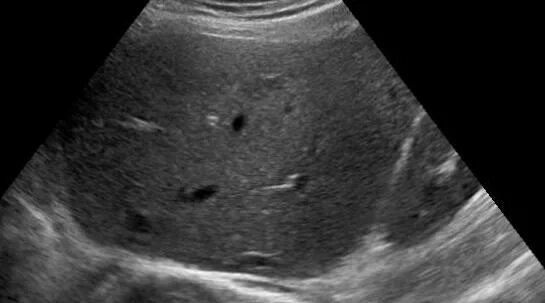

Белое пятно на узи